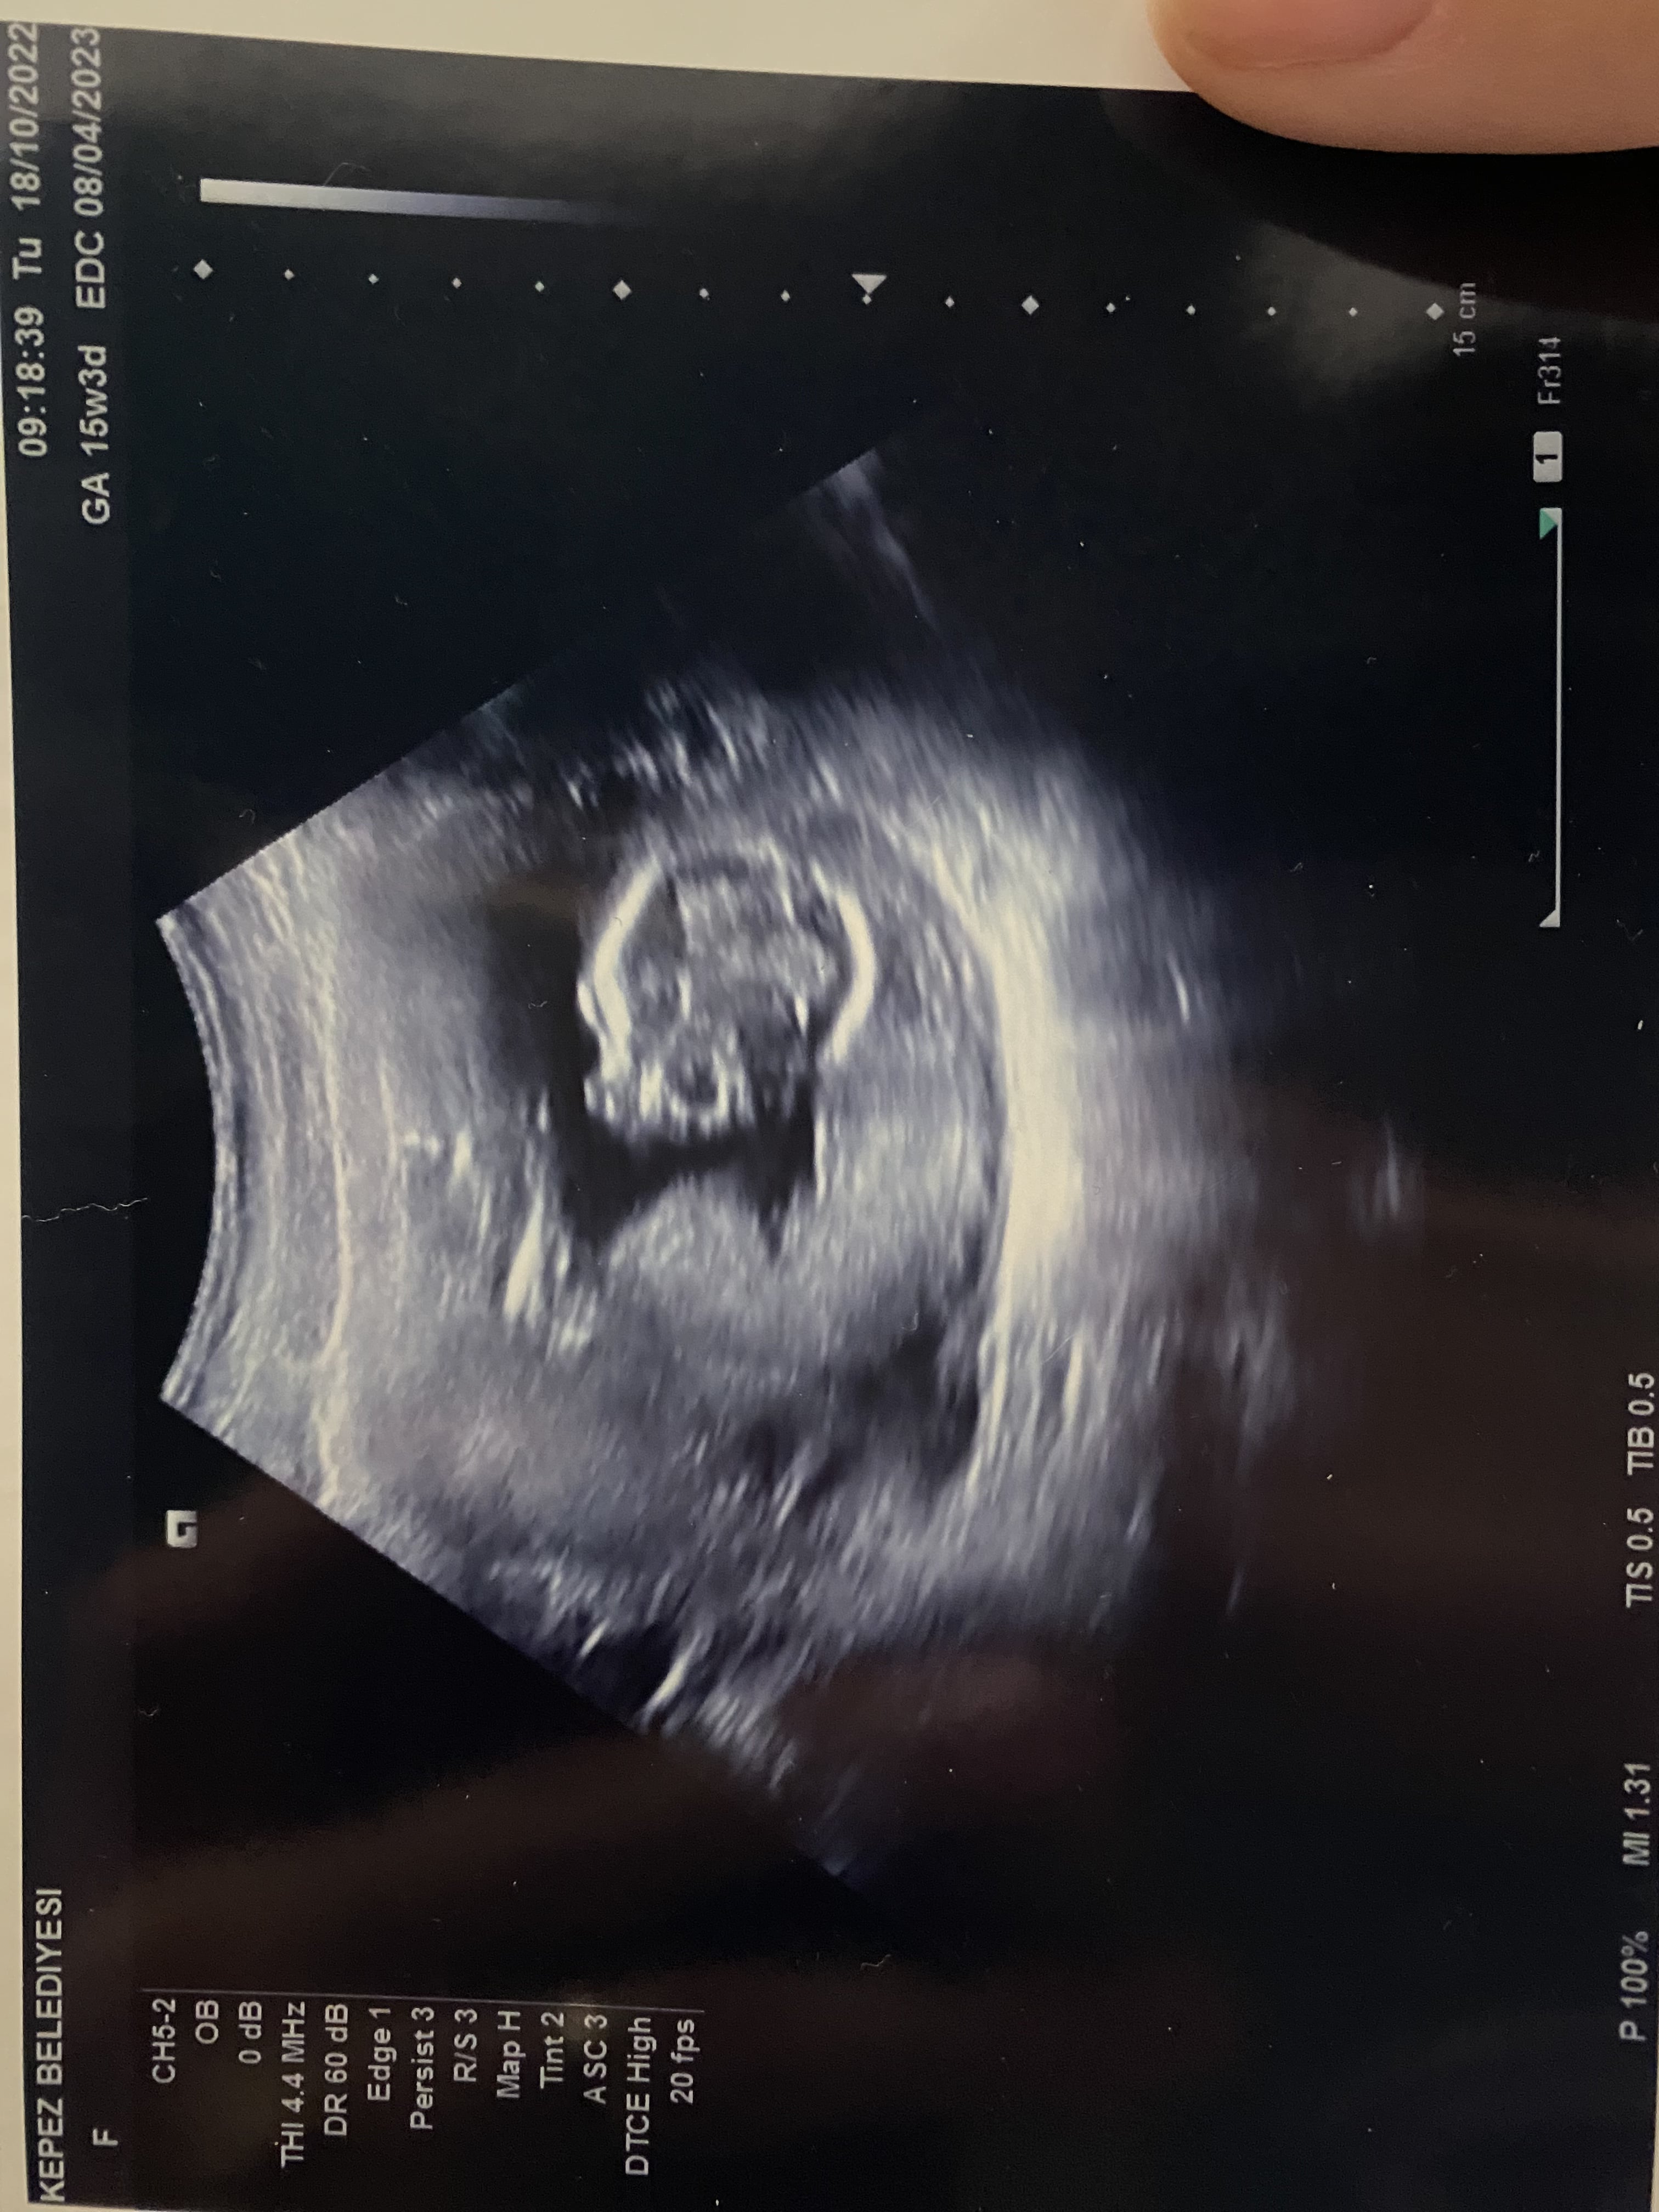

Sorum var Cinsiyetini tahmin edebilir misiniz?15 haftalık 🙏🏻🙏🏻😍😍

Konu Başlığı Cinsiyetini tahmin edebilir misiniz?15 haftalık 🙏🏻🙏🏻😍😍